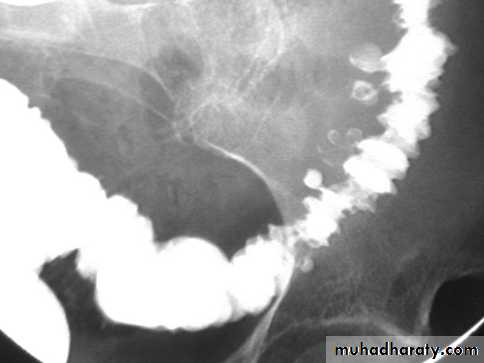

Radiological features of UC :

• Plain film : non specific ,may show marked dilatation of colon due to acute toxic dilatation ( fulminating case ), mural thickening with thumb printing in more sever cases Ba. Enema : usually double contrast allow for detail of colonic mucosa and contra-indicated in toxic dilatation due to the risk of perforation :1)- Widening of pre-sacral space ( Lat. View ).2)-The mucosal ulcers are undermined (Button _shaped ulcer) when most of the mucosa has been lost , island of mucosa remian giveing it ( a pseudo polyp) apperance .3)- Loss of haustration .4)- Narrowing of the colon , in early stage due to spasm , later on due to fibrosis .

• 5)- Shortening of the colon due to fibrosis 6)- In late stage combination of (3 ,4 ,and 5) give rise to Lead pipe appearance .7)- Cobble – stone mucosa due to pseudo-polyposis .8)- Constant narrowing not relieved by relaxant indicate either stricture or malignant changes.

UC

The colon is distended with air

The descending & sigmoid colon are featureless (no haustral pattern)

•

Thumb printing